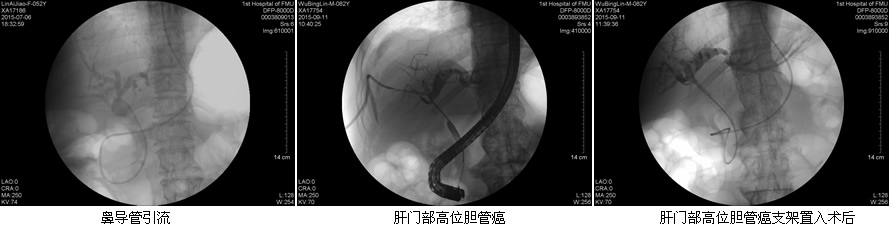

目前ERCP适应症主要包括:原因不明的阻塞性黄疸疑有肝外胆道梗阻者;疑有各种胆道疾病如结石、肿瘤、硬化性胆管炎等诊断不明者;疑有先天性胆道异常或胆囊术后症状再发者;胰腺疾病:胰腺肿瘤、慢性胰腺炎、胰腺囊肿等。在这50余例病例中,包含了内镜下乳头活检术、乳头括约肌切开取石术、胆管内支架引流术、鼻胆管引流术、“三镜”联合治疗胆总管结石等,患者术后无明显并发症发生,获得了良好的疗效,使我院ERCP诊疗技术进入一个崭新的时代。

在工作中,该团队始终坚持“用科研的态度对待每一例患者!”无论是小小的十二指肠乳头活检术,还是难度较大的胃毕Ⅱ术后乳头切开取石术,乃至肝门部高位胆管癌内支架置入术,“安全至上”的理念始终体现在每一位患者身上。无论简单还是复杂,ERCP团队的每一位成员,术前都严格评估适应症和禁忌症,术中规范操作,术后应按预案防治并发症,确保了每一例患者的安全。